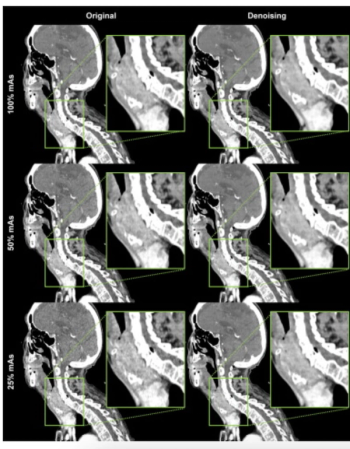

Image quality, sharpness, and contrast with AI-based denoising were significantly enhanced for neck CT in comparison to conventional CT image reconstruction at 100 percent and 50 percent mAs, according to newly published research.